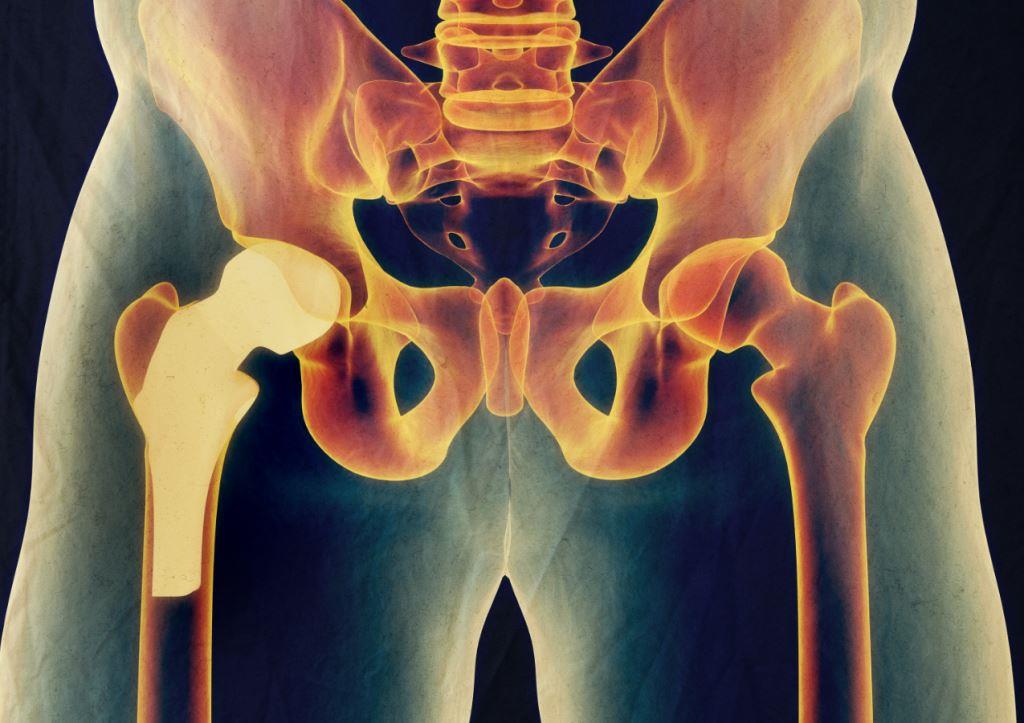

The most common type of hip surgery is hip replacement, also called hip arthroplasty. This procedure involves replacing the damaged hip joint with an artificial joint. Hip surgery can also be done to repair a damaged hip joint, which is called hip resurfacing. It is a less invasive procedure in which only the damaged surface of the ball portion of the joint is removed and replaced.

Hip replacement surgery is a surgical procedure that involves replacing the damaged hip joint with an artificial one. Recovery after hip replacement surgery can be lengthy, especially for older patients. However, most people are expected to fully recover within three months. Patients might need to undergo physical therapy to regain strength in the hip joint.